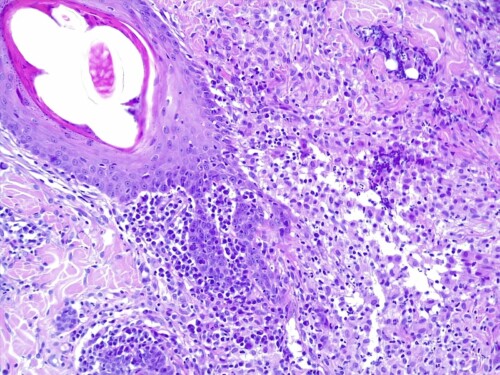

L’épiderme est atrophié, siège d’une importante hyperkératose orthokératosique, intéressant également les follicules pileux qui sont dilatés, comédoneux, avec des tiges pilaires avulsées souvent entourées d’un matériel inflammatoire mêlant granulocytes neutrophiles et des colonies bactériennes de cocci. Dans le derme, on observe au sein des unités annexielles folliculo-sébacées, une atrophie discrète des follicules pileux, des glandes sébacées et des glandes sudorales épitrichiales. Les follicules pileux sont parfois en phase télogène et catagène. La gaine conjonctive des follicules est épaissie, fibro-hyalinisée. Dans le derme, on observe de multiples foyers de métaplasie osseuse avec un derme non-inflammatoire (photos histo).